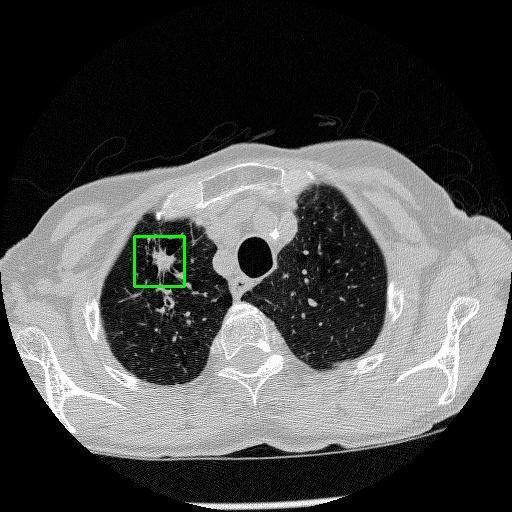

We developed an AI-based system using deep learning models for analyzing lung CT scans to detect and classify pulmonary nodules. We chose the YOLOv11 architecture for its enhanced object detection capability and adapted it specifically for medical imaging, incorporating pixel-level precision and severity classification.

Classification into three severity levels with colored bounding boxes.

Designed a severity classification system that categorizes nodules into null, moderate, and severe using colored bounding boxes, assisting in rapid clinical decision-making.